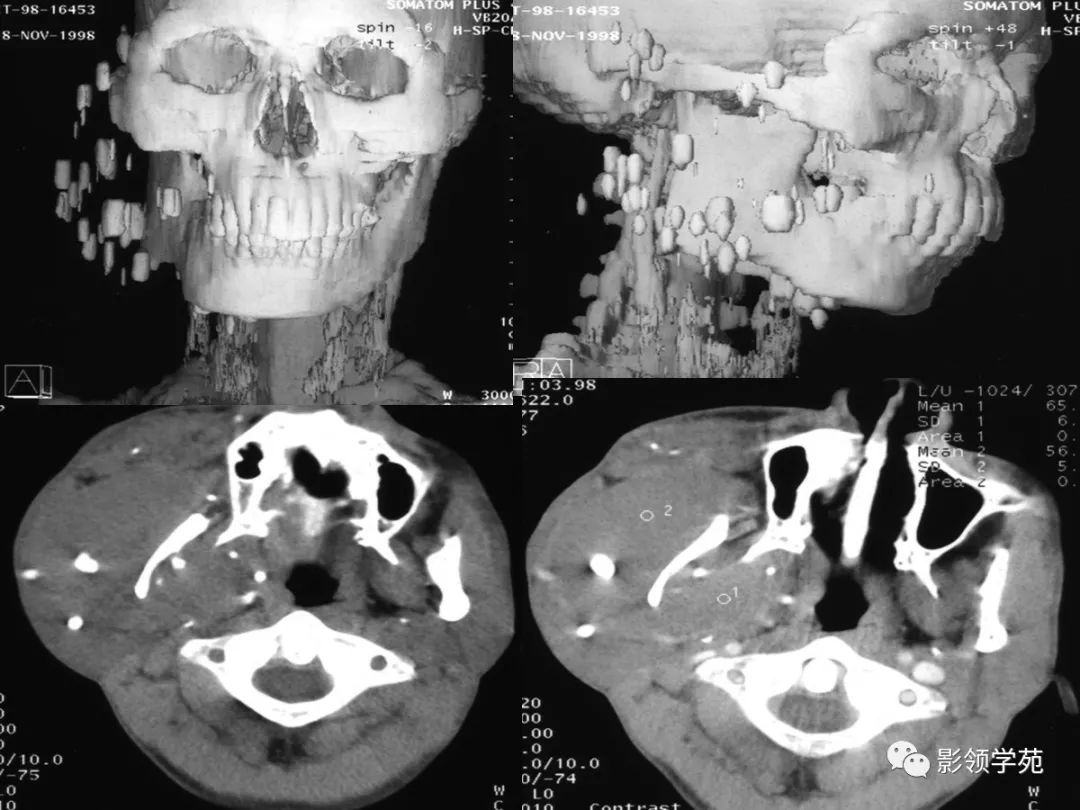

颈部常见疾病影像诊断

- 血管瘤

- 颈动脉体瘤